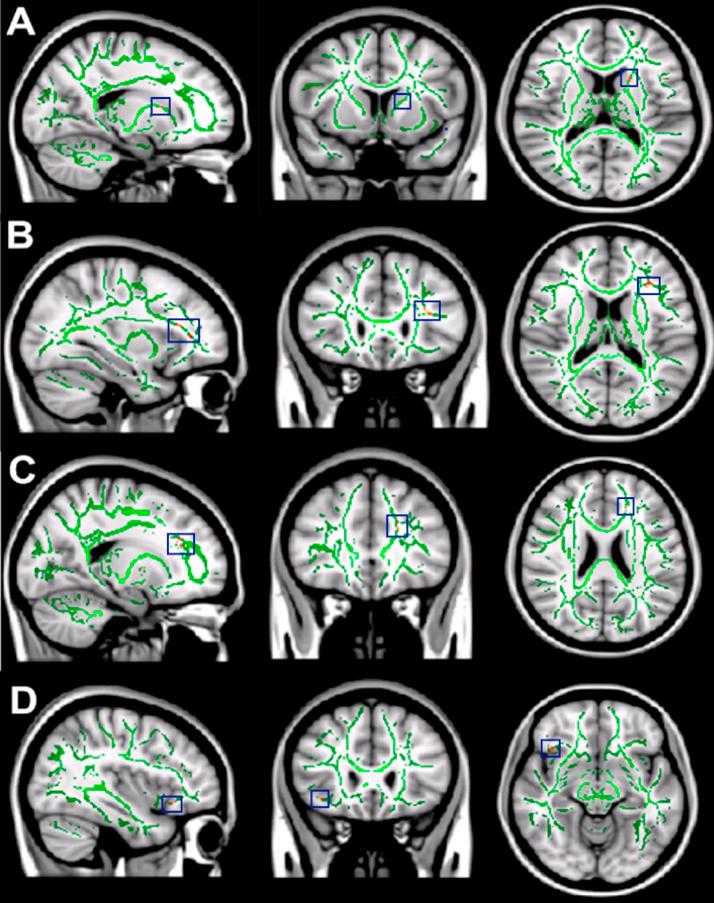

Self-imposed short sleep durations are increasingly commonplace in society, and have considerable health and performance implications for individuals. Reduced sleep duration over multiple nights has similar behavioural effects to those observed following acute total sleep deprivation, suggesting that lack of sleep affects brain function cumulatively. A link between habitual sleep patterns and functional connectivity has previously been observed, and the effect of sleep duration on the brain's intrinsic functional architecture may provide a link between sleep status and cognition. However, it is currently not known whether differences in habitual sleep patterns across individuals are related to changes in the brain's white matter, which underlies structural connectivity. In the present study we use diffusion-weighted imaging and a group comparison application of tract based spatial statistics (TBSS) to investigate changes to fractional anisotropy (FA) and mean diffusivity (MD) in relation to sleep duration and quality, hypothesising that white matter metrics would be positively associated with sleep duration and quality. Diffusion weighted imaging data was acquired from a final cohort of 33 (23-29 years, 10 female, mean 25.4 years) participants. Sleep patterns were assessed for a 14 day period using wrist actigraphs and sleep diaries, and subjective sleep quality with the Pittsburgh Sleep Quality Index (PSQI). Median splits based on total sleep time and PSQI were used to create groups of shorter/longer and poorer/better sleepers, whose imaging data was compared using TBSS followed by post-hoc correlation analysis in regions identified as significantly different between the groups There were significant positive correlations between sleep duration and FA in the left orbito-frontal region and the right superior corona radiata, and significant negative correlations between sleep duration and MD in right orbito-frontal white matter and the right inferior longitudinal fasciculus. Improved sleep quality was positively correlated with FA in left caudate nucleus, white matter tracts to the left orbito-frontal region, the left anterior cingulum bundle and the white matter tracts associated with the right operculum and insula, and negatively correlated with MD in left orbito-frontal white matter and the left anterior cingulum bundle. Our findings suggest that reduced cumulative total sleep time (cTST) and poorer subjective sleep quality are associated with subtle white matter micro-architectural changes. The regions we identified as being related to habitual sleep patterns were restricted to the frontal and temporal lobes, and the functions they support are consistent with those which have previously been demonstrated as being affected by short sleep durations (e.g., attention, cognitive control, memory). Examining how inter-individual differences in brain structure are related to habitual sleep patterns could help to shed light on the mechanisms by which sleep habits are associated with brain function, behaviour and cognition, as well as potentially the networks and systems responsible for variations in sleep patterns themselves.

自我设定的短睡眠时间在社会中越来越普遍,对个人的健康和表现有相当大的影响。多个晚上睡眠时长减少所产生的行为影响,与急性完全睡眠剥夺后观察到的影响相似,这表明睡眠不足会累积影响大脑功能。此前已观察到习惯性睡眠模式与功能连接之间存在联系,而睡眠时间对大脑内在功能结构的影响可能为睡眠状态与认知之间提供一种联系。然而,目前尚不清楚个体之间习惯性睡眠模式的差异是否与大脑白质的变化有关,而白质是结构连接的基础。在本研究中,我们使用扩散加权成像和基于束的空间统计学(TBSS)的组间比较应用,来研究分数各向异性(FA)和平均扩散率(MD)与睡眠时间和质量相关的变化,假设白质指标与睡眠时间和质量呈正相关。扩散加权成像数据是从33名(年龄在23 - 29岁之间,10名女性,平均25.4岁)参与者的最终队列中获取的。使用腕部活动记录仪和睡眠日记对睡眠模式进行了为期14天的评估,并使用匹兹堡睡眠质量指数(PSQI)评估主观睡眠质量。基于总睡眠时间和PSQI的中位数分割用于创建短/长睡眠者和差/好睡眠者组,对他们的成像数据使用TBSS进行比较,随后在组间差异显著的区域进行事后相关分析。睡眠时间与左侧眶额区域和右侧放射冠上部的FA之间存在显著正相关,而睡眠时间与右侧眶额白质和右侧下纵束的MD之间存在显著负相关。睡眠质量改善与左侧尾状核、连接至左侧眶额区域的白质束、左侧前扣带回束以及与右侧岛盖和脑岛相关的白质束中的FA呈正相关,与左侧眶额白质和左侧前扣带回束中的MD呈负相关。我们的研究结果表明,累积总睡眠时间(cTST)减少和主观睡眠质量较差与白质微观结构的细微变化有关。我们确定的与习惯性睡眠模式相关的区域局限于额叶和颞叶,它们所支持的功能与先前已证明受短睡眠时间影响的功能(如注意力、认知控制、记忆)一致。研究大脑结构的个体差异如何与习惯性睡眠模式相关,有助于阐明睡眠习惯与大脑功能、行为和认知相关的机制,以及潜在地揭示负责睡眠模式变化的网络和系统。